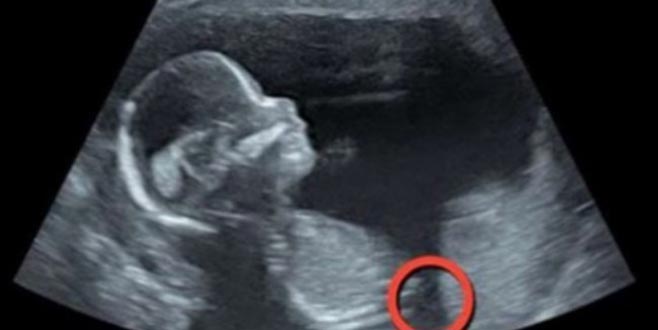

Tıpta devrim! Bebeği rahimden çıkarıp yerine geri koydular

İngiltere'de hamile bir kadının bebeğinin gelişimsel sorunları olduğu tespit edildi. Hayati bir problemi olan bebek,